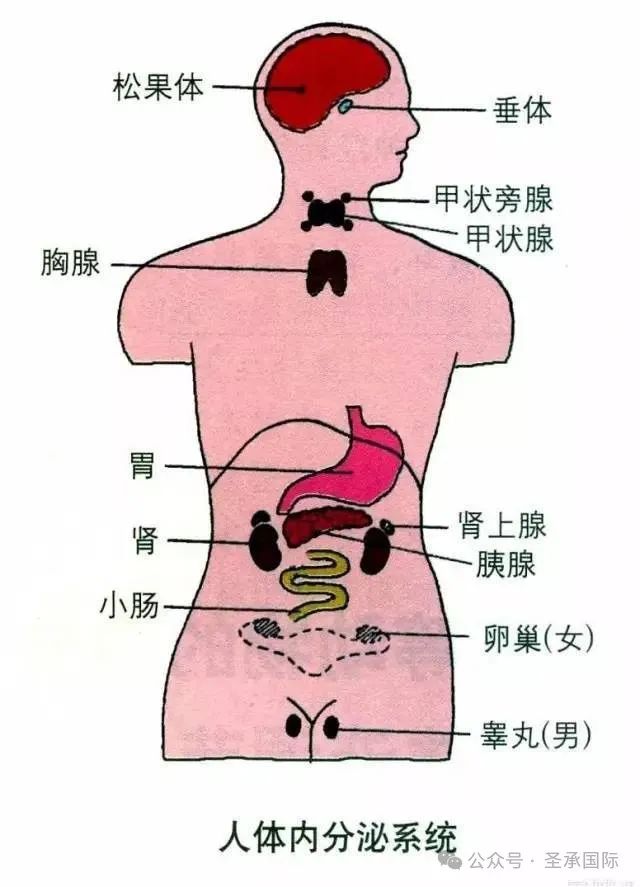

八大腺体指的是人体内能合成和分泌人体重要激素的八大内分泌腺体。它们包括位于人体脑部的垂体和松果体;位于颈部的甲状腺和甲状旁腺;位于胸部心脏旁边的胸腺;位于腹部能产生胰岛素的胰腺;位于两侧肾脏上方的肾上腺;还有分泌男女性激素的性腺,男性的性腺是睾丸,女性的性腺是卵巢。

荷尔蒙掌控着人的生长、发育、衰老、疾病及死亡。人体内共有“八大腺体”,它们能合成和分泌人体的重要激素,如果激素在腺体内停止分泌,生命就会难以维持。在调理身体的荷尔蒙平衡时,往往会从人体的八大腺体入手,这两者之间有着密不可分的关系。

八大腺体指的是人体内能合成和分泌人体重要激素的八大内分泌腺体。它们包括位于人体脑部的垂体和松果体;位于颈部的甲状腺和甲状旁腺;位于胸部心脏旁边的胸腺;位于腹部能产生胰岛素的胰腺;位于两侧肾脏上方的肾上腺;还有分泌男女性激素的性腺,男性的性腺是睾丸,女性的性腺是卵巢。

荷尔蒙掌控着人的生长、发育、衰老、疾病及死亡。人体内共有“八大腺体”,它们能合成和分泌人体的重要激素,如果激素在腺体内停止分泌,生命就会难以维持。在调理身体的荷尔蒙平衡时,往往会从人体的八大腺体入手,这两者之间有着密不可分的关系。